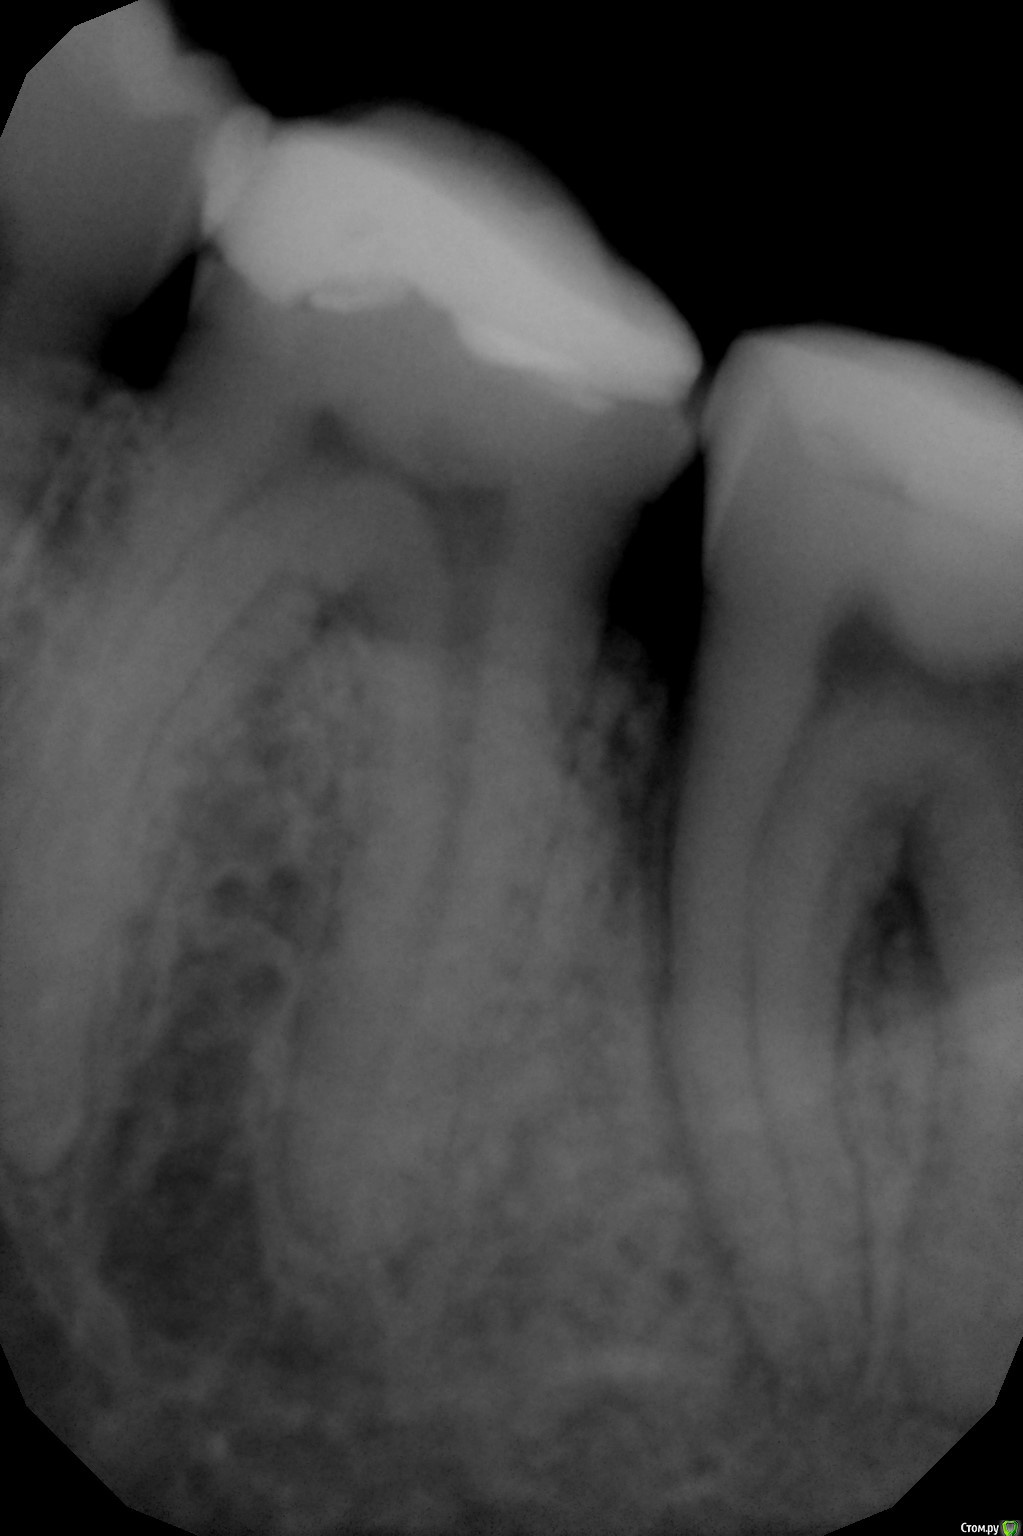

Yulechka1986 Опубликовано 12 сентября, 2016 Поделиться Опубликовано 12 сентября, 2016 Уважаемые коллеги! Прошу совета! Практически интактная семерка, 3.7. обратился пациент по поводу скола пломбы, боли при накусывании. После лечения боли продолжаются, на снимке обнаружена гранулирующее изменение костной ткани. Депульпировать? Как лечить гранулему? Выводить туда кальций? Ссылка на комментарий

Yulechka1986 Опубликовано 12 сентября, 2016 Автор Поделиться Опубликовано 12 сентября, 2016 Почти интактный? Ну это Вы погорячились. Я никаких гранулем на апексах не вижу. Неплохо бы снимок перевернуть.Тест на витальность делали?Мне карман дистально не нравитсядумаете пломба близко к рогу пульпы? Карман есть, между корней разряжение костной ткани.. Ссылка на комментарий

vse32 Опубликовано 12 сентября, 2016 Поделиться Опубликовано 12 сентября, 2016 Похоже начинаю понимать. 37 это тот, что обрезанный? Мне кажется там паро проблемы есть. И не без участия плохого контакта 36-37.Тест на витальность нужен. Ссылка на комментарий

Бардо Опубликовано 12 сентября, 2016 Поделиться Опубликовано 12 сентября, 2016 (изменено) Видимо справа. Депульпировать не надо. Делайте адекватные реставрации на 6 и 7, устраняйте проблему с пародонтом Изменено 12 сентября, 2016 пользователем Бардо 2 Ссылка на комментарий

vse32 Опубликовано 19 сентября, 2016 Поделиться Опубликовано 19 сентября, 2016 это вкладки? да пациент говорит на холодное боли проходят но сегодня попало сладкое и сильно разболелось Так на 36 кариес, вот и боли на сладкое в том числе. Ссылка на комментарий